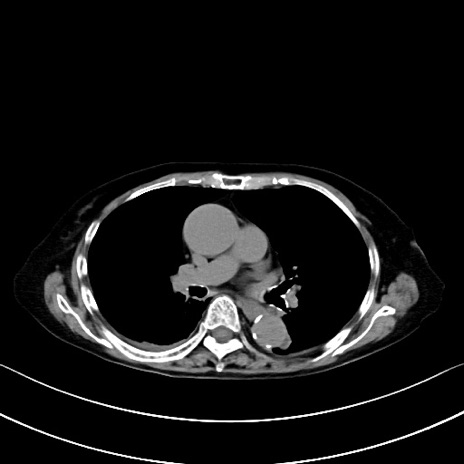

症例40(横断像)他院1日前

横断像

他院CT